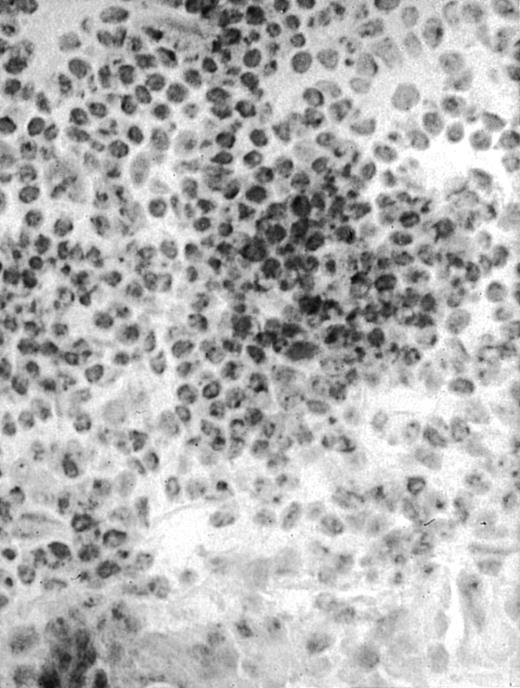

To explore the mechanisms of the protection from BCL growth, histologic analysis was performed on tumor tissue from mice treated with ST40L, ST, or PBS alone. In the mice treated with PBS alone, no cellular infiltrate expressing FasL was observed in the surrounding tissues and inside the BCL region (Figure 4A and D). In contrast, infiltrating lymphocytes expressing FasL were observed around the vessels and also scattered in the smaller tumor tissues in the mice treated with ST (Figure 4B and E). Small hard nodules (2-5 mm in diameter) were observed at the SC injection sites of the long-term survival mice that had been treated with ST40L. On histologic analysis, these small nodules were confirmed to be the result of an accumulation of lymphocytes, and not BCL cells (Figure 4C). These lymphocytes were also found to be strongly positive for FasL expression (Figure 4F). On the other hand, lymphocytes infiltrating in the nodules were stained by either CD4+ Ab or CD8+ Ab, but the ratio of CD4+ and CD8+ cells was not 1-sided (data not shown).

Histologic analysis of A20 tumors excised 21 days postchallenge from BALB/c mice immunized with ST40L.

(A) HE stain of a BCL region in a mouse treated with PBS alone. (B) HE stain of a smaller BCL region in a mouse treated with ST. (C) HE stain of a small hard nodule at the SC injection site in a mouse treated with ST40L. (D) Fas ligand staining of a BCL region in a mouse treated with PBS alone. (E) Fas ligand staining of a BCL region in a mouse treated with ST. (F) Fas ligand staining of a small hard nodule at the SC injection site in a mouse treated with ST40L. Original magnifications are ×400.